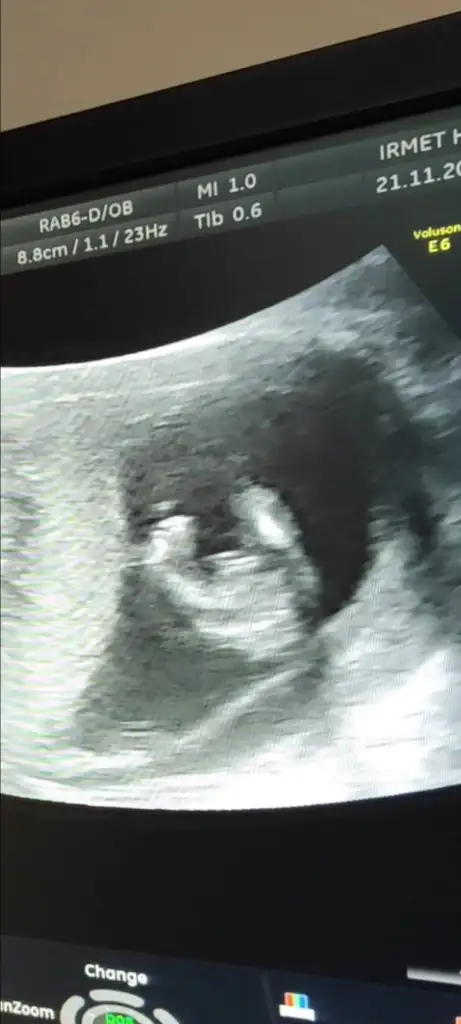

Bunlarda bugünkü ultrasonlar 🤣 ne görüyorsunuz

Ben hiç anlamıyorum nubuda göremedim bı ilk resimde var gibi ordan kız dedim bende 🤭

Bende anlammaam ama seninki kiza cok bnzyoo .. benim kizlrn ultrsna benzyoo backlr dumduz klca asagya dogru .. erkkelr kalcadan biraz cikntisi yukri dogru